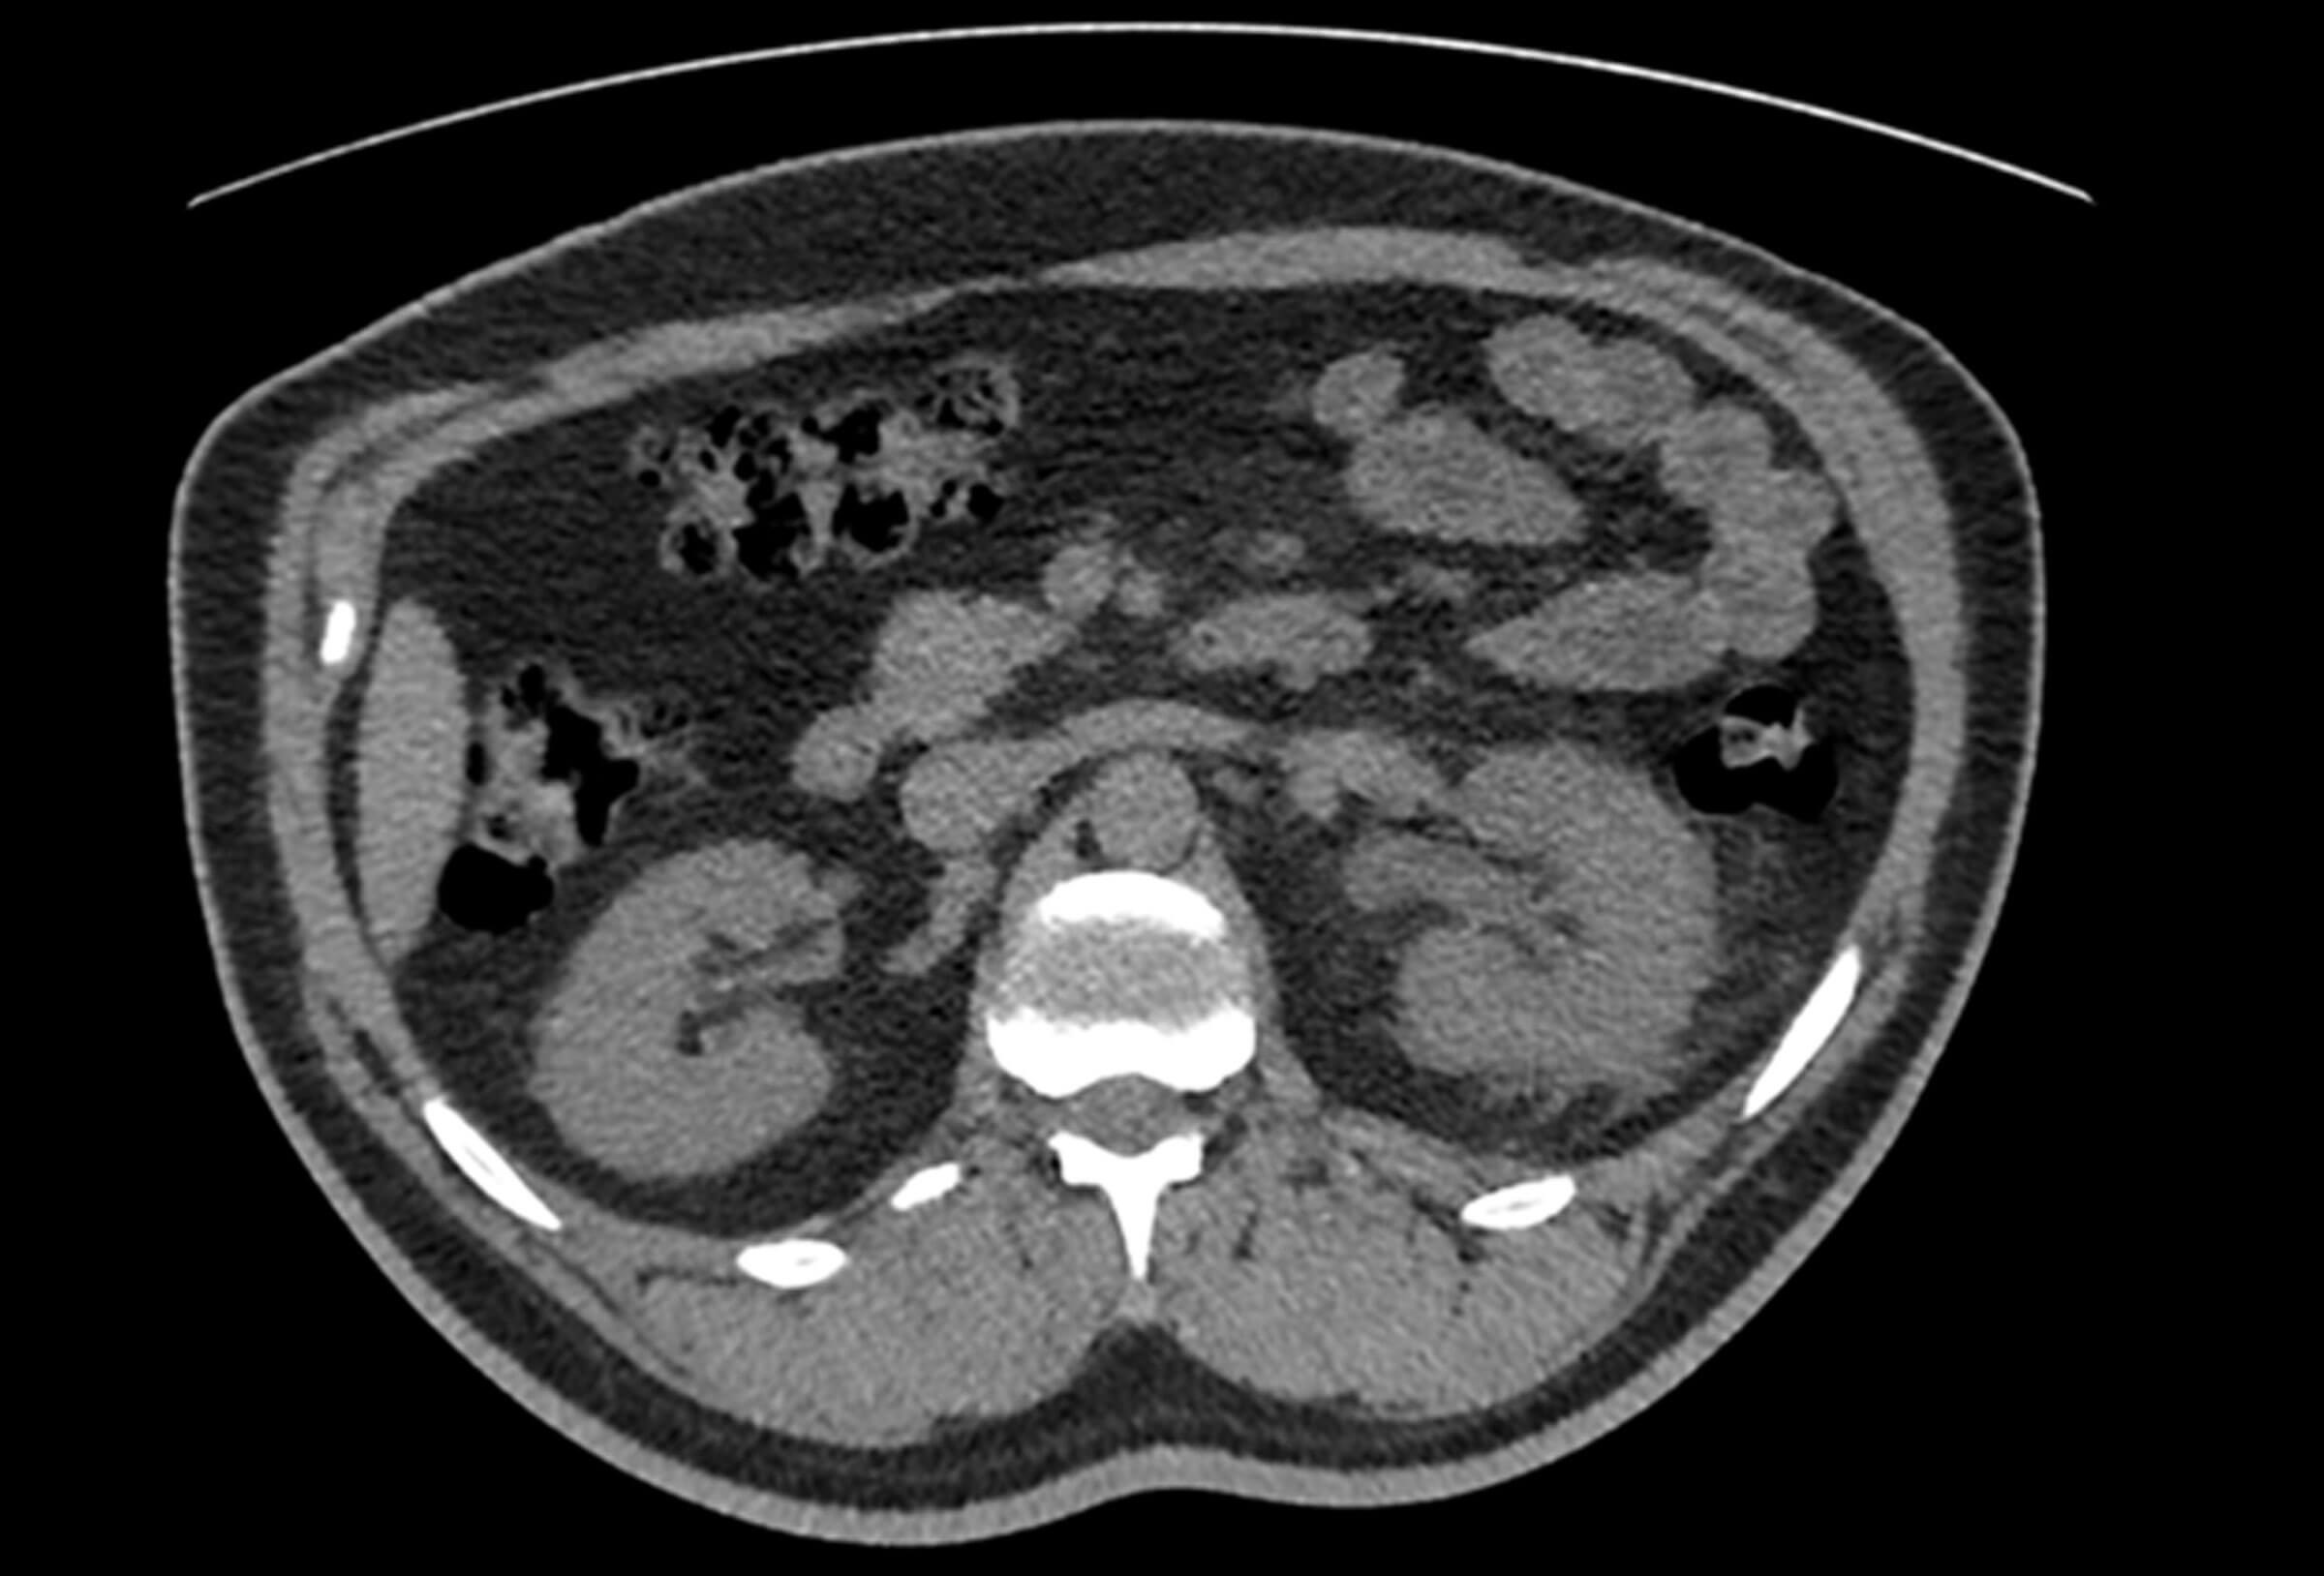

Figure 2.

- Which features typically seen in upper urinary tract obstruction are demonstrated in Figure 2?

2. The corresponding axial image at the level of the renal hilum, with the patient scanned in the prone position, shows signs of obstruction: (mild) left hydronephrosis with associated perinephric fat stranding and small amount of perinephric fluid.